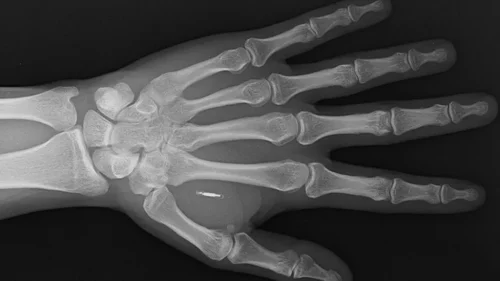

Spoiler alert: “Augmented society” is a fast track toward normalizing the implanting of microchips.

- “As scary as chip implants may sound, they form part of a natural evolution that wearables once underwent. Hearing aids or glasses no longer carry a stigma. They are accessories and are even considered a fashion item. Likewise, implants will evolve into a commodity.”